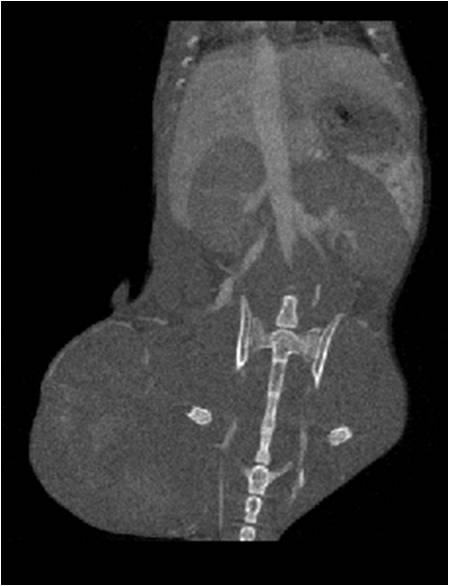

檢測案例

小鼠股骨

超高分辨率模式下像素大小為9μm。

A軸向和矢狀面顯示小鼠股骨結構。

B用鈦材料植入的穿過骨頭的冠狀切片